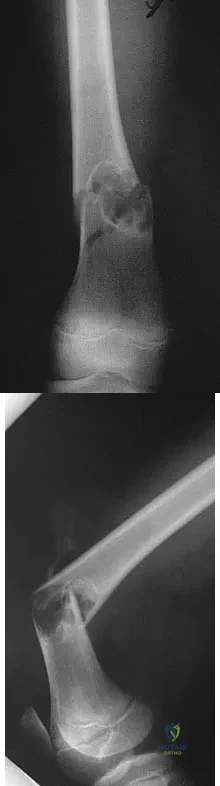

Question 33 High Yield

What is the primary mechanism of injury for the fracture shown in Figures 33a and 33b?

Detailed Explanation